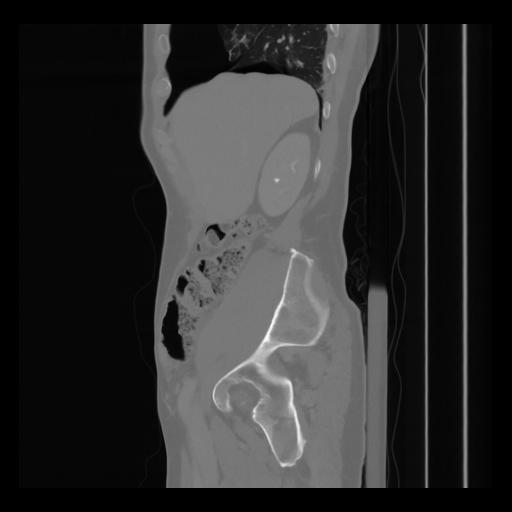

36 CUERPO,CE,Sagittal,3.000,CUERPO,Sagittal,